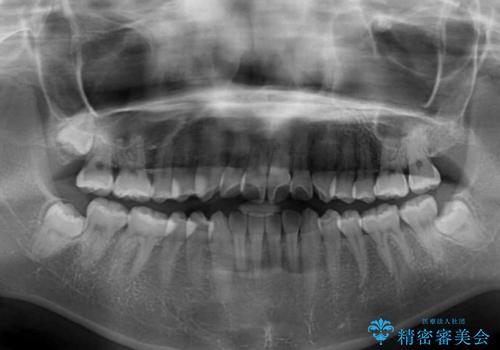

- 前歯の捻れと、ちょっとした出っ張りを気にして来院された患者様です。

歯と歯の間を削る(IPR)ことでデコボコを解消し、インビザラインで整えることとしました。

インビザライン治療特有の奥歯が接触しない時期が続き、当初予定よりも期間がかかりましたが、最終的には安定した咬み合わせと、整った前歯になりました。